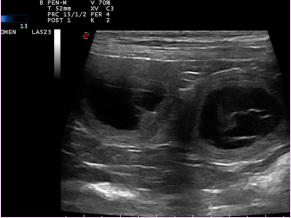

Wir freuen uns auf Welpen von Azu und Hobbit, der heutige Ultraschall war positiv